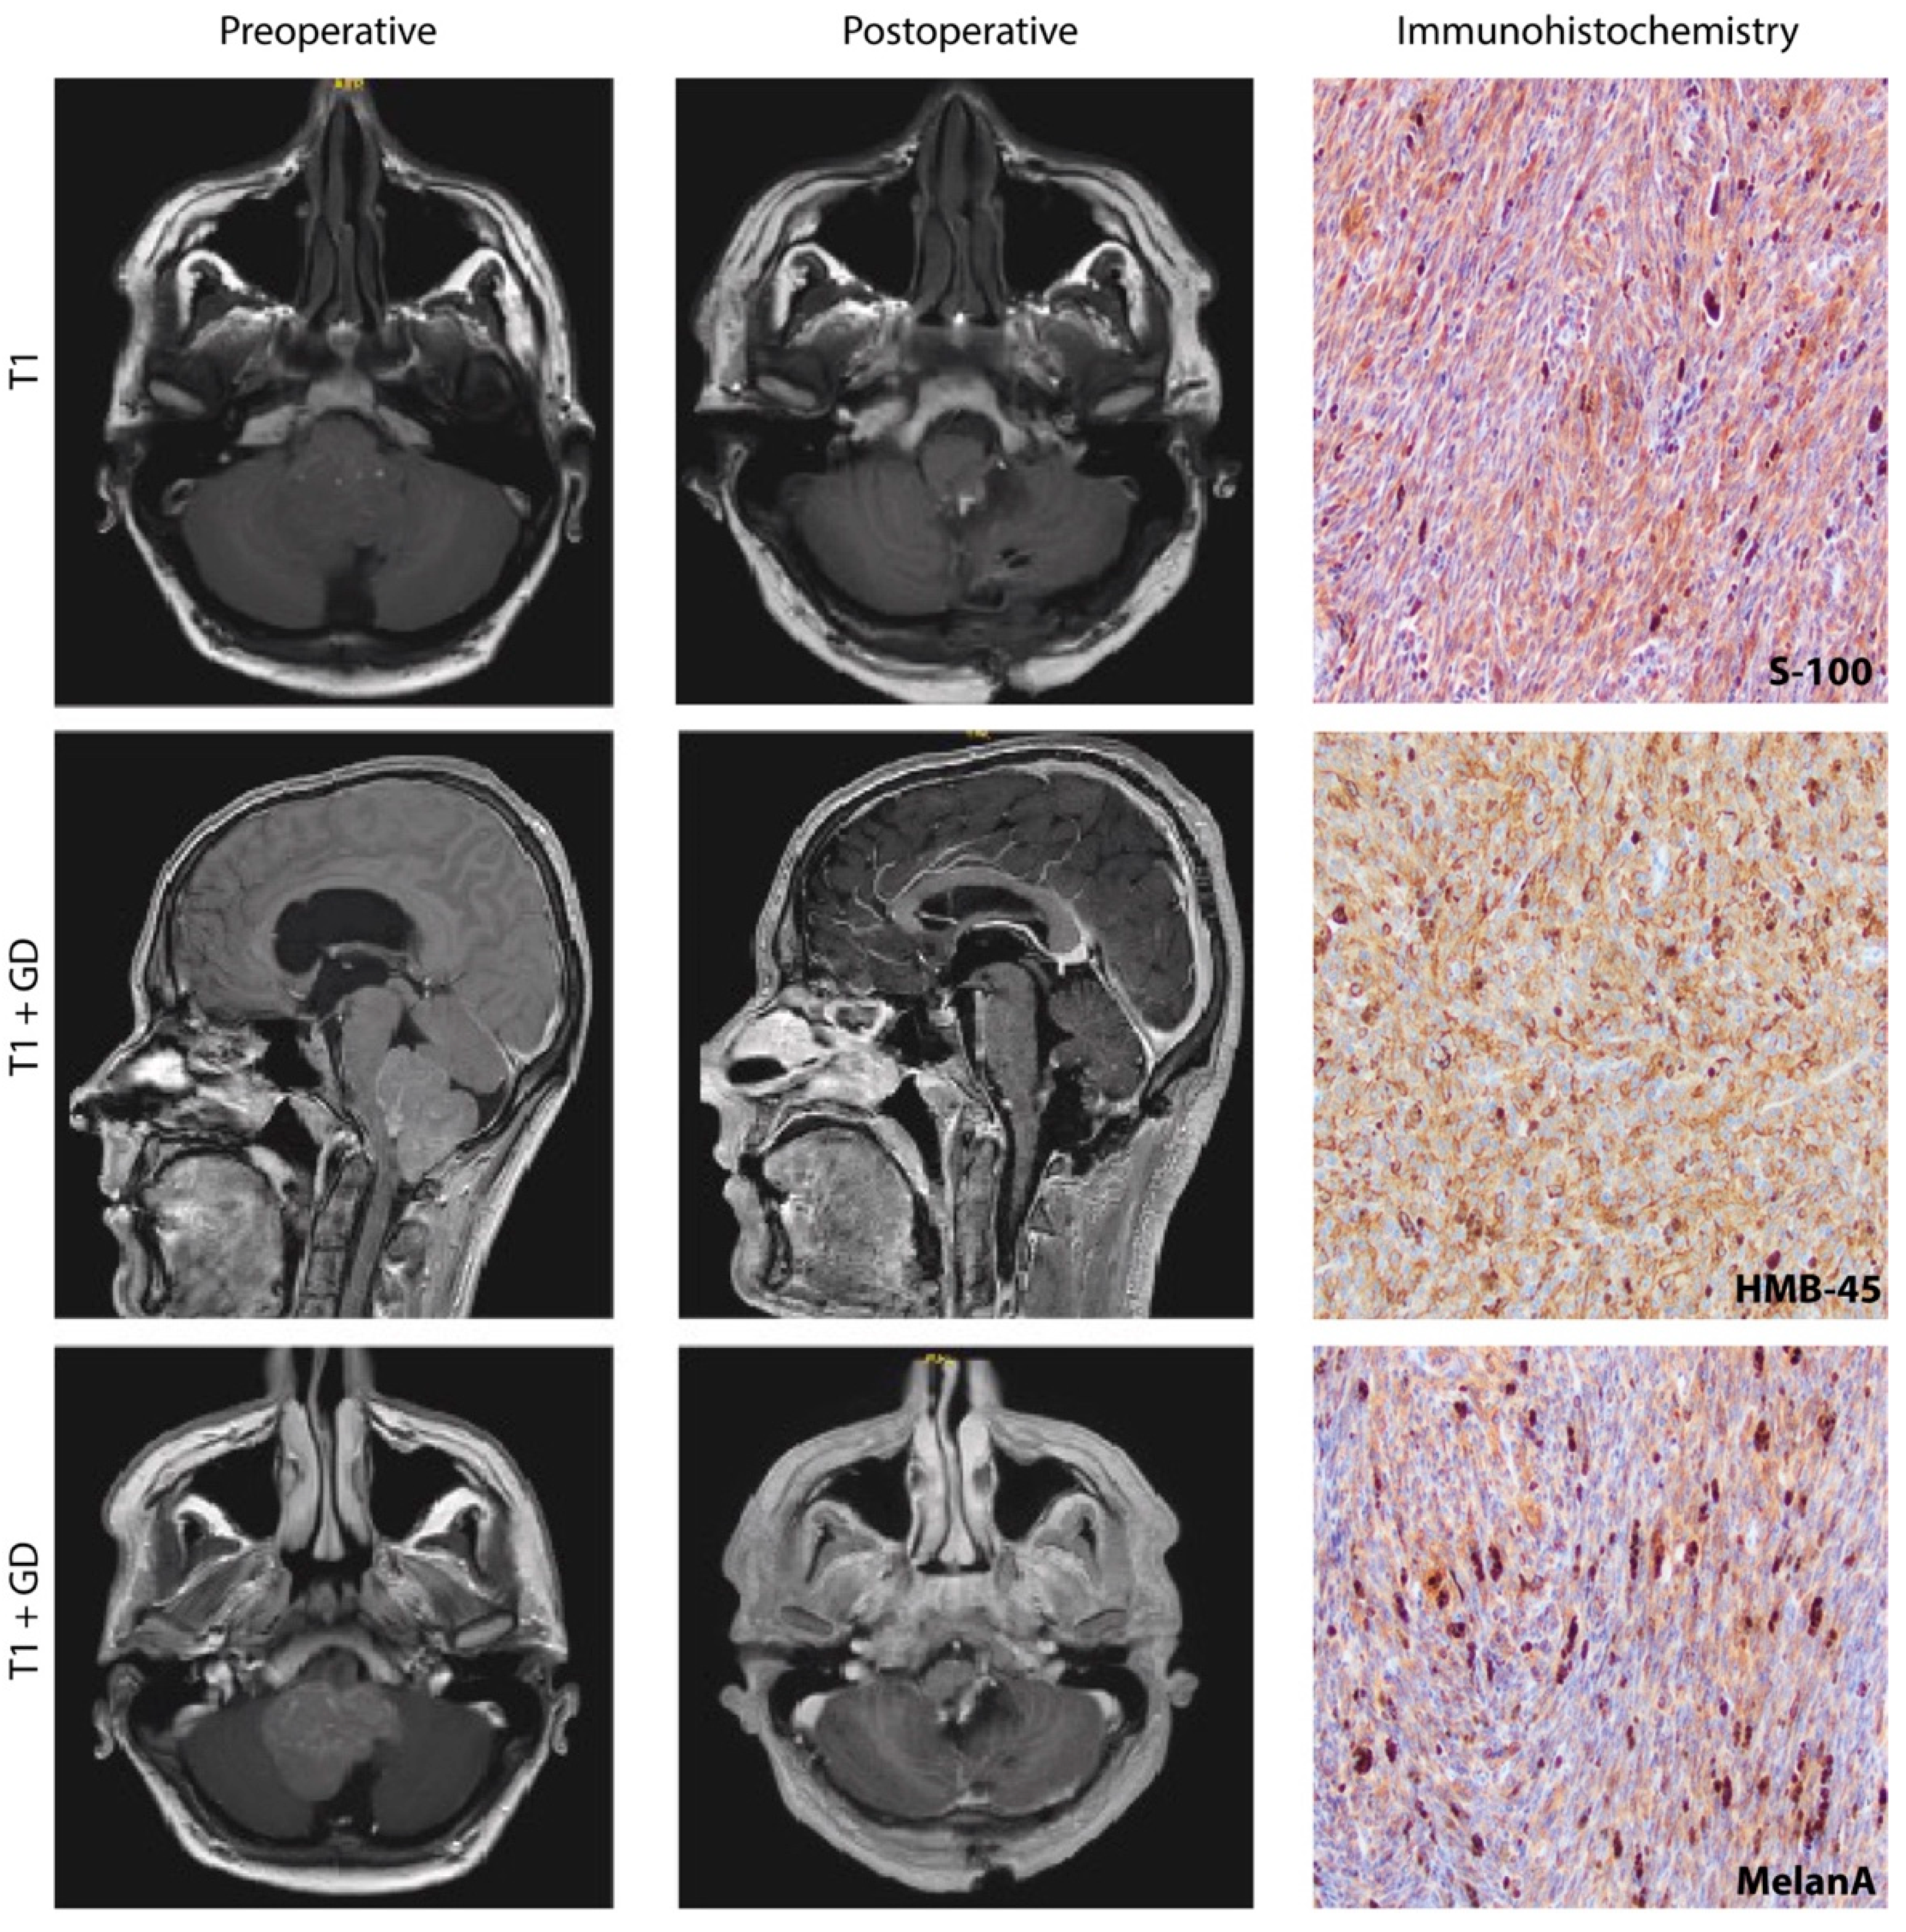

Abstract

1. Introduction